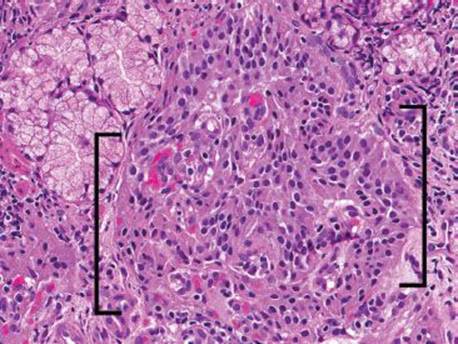

Small bowel biopsies can be treacherous because of all the potential hiding places for sneaky diagnoses (Fig. 3.341). Microscopic neuroendocrine tumors, for example, can be easily obscured by a busy and “abused” small bowel biopsy (Figs. 3.341–3.345) and yet diligent inspection is critical as even microscopic neuroendocrine tumors can behave aggressively. When dealing with a challenging case of crushed and cauterized tissue, consider a chromogranin and synaptophysin immunostain, deeper sections, or ask for a repeat biopsy.

Figure 3.343 Sneaky neuroendocrine tumor. At this power, note the Brunner glands are pushed apart by an expansile process, an alarming finding that deserves close inspection. Brackets highlight pockets of neoplastic cells arranged in nests, suggestive of a neuroendocrine neoplasm. The diagnosis of this sneaky neuroendocrine tumor is particularly challenging in such a busy background.

Figure 3.344 Sneaky neuroendocrine tumor. Higher power. The neoplastic cells (brackets) are poorly preserved, crushed, and could easily be mistaken for crushed lymphocytes if not carefully inspected at higher power.